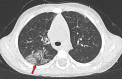

Chest CT has a potential role in the diagnosis, detection of complications, and prognostication of coronavirus disease 2019 (COVID-19). Implementation of appropriate precautionary safety measures, chest CT protocol optimization, and a standardized reporting system based on the pulmonary findings in this disease will enhance the clinical utility of chest CT. However, chest CT examinations may lead to both false-negative and false-positive results. Furthermore, the added value of chest CT in diagnostic decision making is dependent on several dynamic variables, most notably available resources (real-time reverse transcription-polymerase chain reaction [RT-PCR] tests, personal protective equipment, CT scanners, hospital and radiology personnel availability, and isolation room capacity) and the prevalence of both COVID-19 and other diseases with overlapping manifestations at chest CT. Chest CT is valuable to detect both alternative diagnoses and complications of COVID-19 (acute respiratory distress syndrome, pulmonary embolism, and heart failure), while its role for prognostication requires further investigation. The authors describe imaging and managing care of patients with COVID-19, with topics including (a) chest CT protocol, (b) chest CT findings of COVID-19 and its complications, (c) the diagnostic accuracy of chest CT and its role in diagnostic decision making and prognostication, and (d) reporting and communicating chest CT findings. The authors also review other specific topics, including the pathophysiology and clinical manifestations of COVID-19, the World Health Organization case definition, the value of performing RT-PCR tests, and the radiology department and personnel impact related to performing chest CT in COVID-19. ©RSNA, 2020.